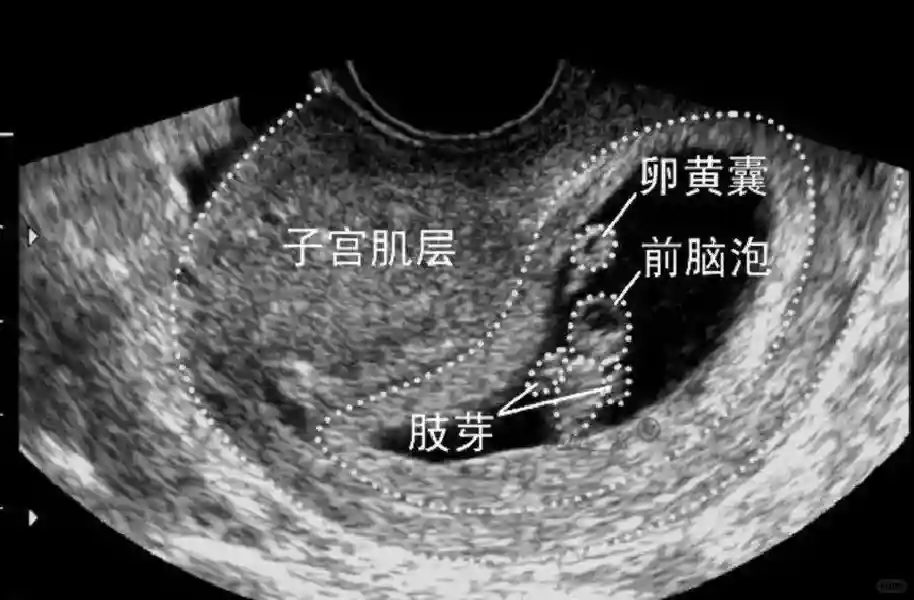

2??卵黃囊:是妊娠囊內(nèi)第一個(gè)解剖結(jié)構(gòu),直徑<7mm。表現(xiàn)為小環(huán)狀,中央為無(wú)回聲,囊壁薄,內(nèi)透聲好。卵黃囊位于胚胎旁胚外體腔內(nèi)。卵黃囊通常在孕5-6周時(shí)出現(xiàn),5-10周穩(wěn)步增長(zhǎng),一般不超過(guò)7mm,至12周消失。妊娠囊的大小與卵黃囊之間有一定關(guān)系,妊娠囊平均直徑> 8 mm 時(shí),經(jīng)陰道超聲均應(yīng)顯示卵黃囊,妊娠囊平均直徑> 18 mm 時(shí),經(jīng)腹超聲均應(yīng)顯示卵黃囊。

3??胚胎:胚胎通常在6-7周時(shí)可以為超聲顯示,起初為胎芽,表現(xiàn)為卵黃囊一側(cè)局部組織增厚,達(dá)到1 -2 mm 時(shí)才有可能為超聲測(cè)量出來(lái)。達(dá)4-5mm時(shí)可見(jiàn)胎心搏動(dòng),相應(yīng)孕周為6-6.5周,妊娠囊大小為13-18mm。胚芽長(zhǎng)度≥7㎜時(shí)仍未見(jiàn)心管搏動(dòng),提示胚胎停止發(fā)育。胚胎的出現(xiàn)和妊娠囊直徑的關(guān)系:妊娠囊直徑> 16 mm 時(shí),經(jīng)陰道超聲應(yīng)顯示胚胎。妊娠囊直徑> 25 mm 時(shí),經(jīng)腹超聲均應(yīng)顯示胚胎。

5??羊膜:早孕期羊膜囊菲薄,超聲常不能顯示。孕7周以后加大增益或者用高頻超聲可以顯示羊膜。羊膜囊位于絨毛膜內(nèi),胚胎位于羊膜囊內(nèi)。隨著胚胎增長(zhǎng),羊水增多,羊膜囊增大,孕12-16周時(shí),羊膜與絨毛膜全部融合,胚外體腔消失。宮腔線(xiàn)一側(cè)內(nèi)膜內(nèi)一圓形增強(qiáng)回聲區(qū),中央有小囊狀液性暗區(qū),宮腔線(xiàn)局部突起變形,稱(chēng)蛻膜內(nèi)征,用于判斷早早孕。